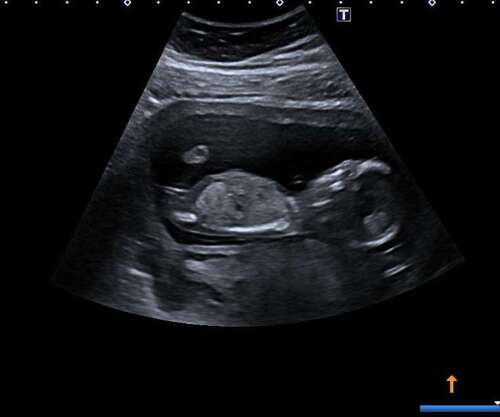

We hebben deze week onze geslachtsecho, super spannend! Deze echo was gemaakt met 13+2, wil iemand nog een gokje wagen? :)

We hebben deze week onze geslachtsecho, super spannend! Deze echo was gemaa ...

Meisje

Goed geraden hier, we krijgen een meisje! 💖🥰